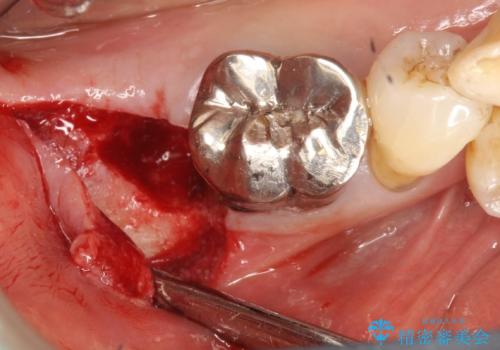

歯周病でぐらぐらになってしまった奥歯を抜歯し、残る骨の高さを鑑みてショートインプラントを選択しました。

インプラントの種類:Bicon